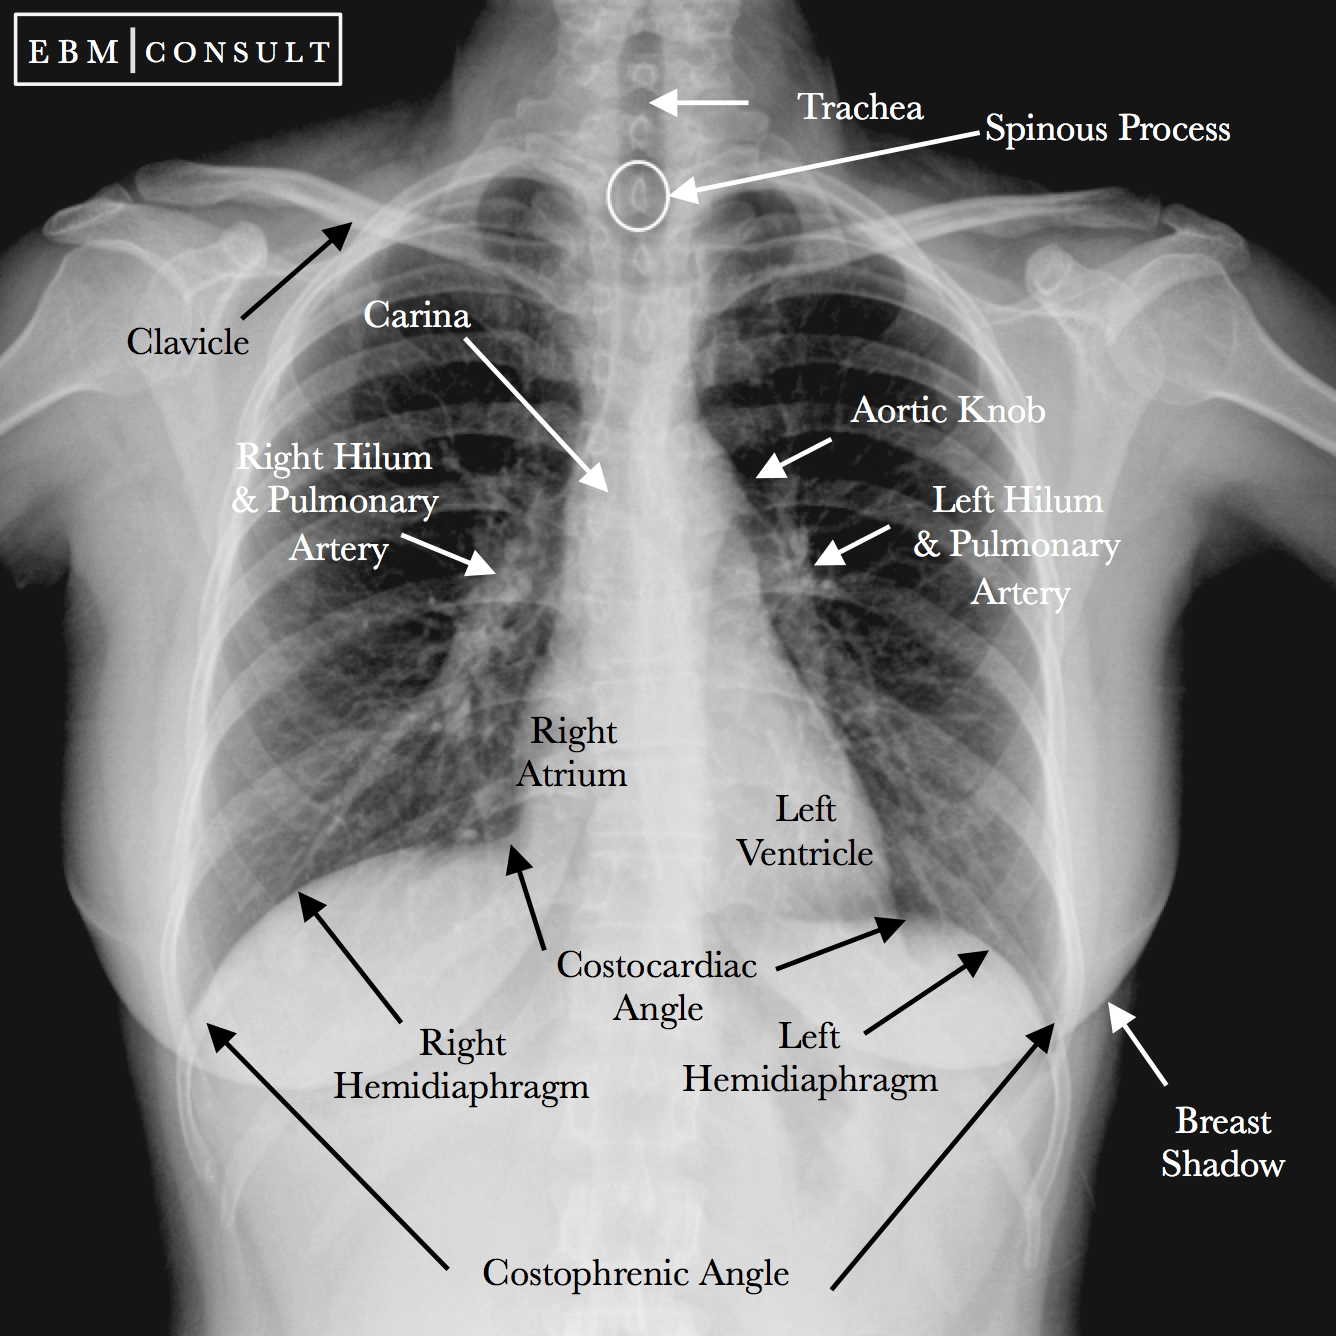

Normal Chest Xray Labeled